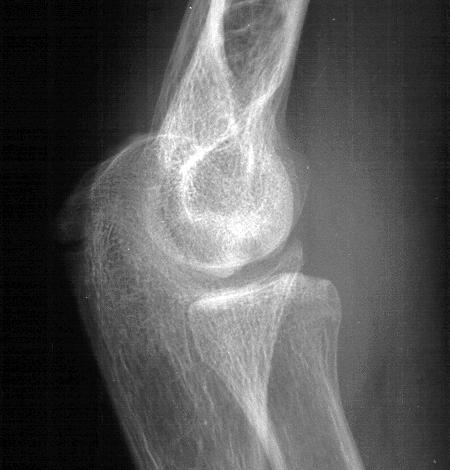

Initial injury: supracondylar fracture in a 9 year old:

Click for larger image